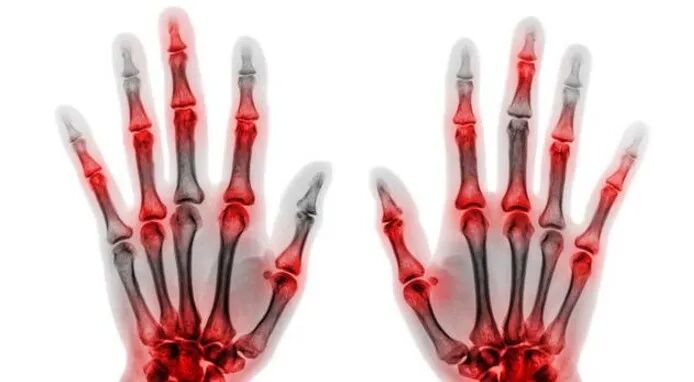

类风湿关节炎与强直性脊任炎有何区别?